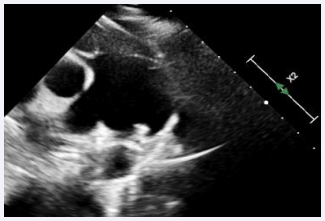

Procedure was done under general anesthesia. Right femoral artery and vein, along with left femoral venous access, were established and 6F sheaths were inserted. A 6F pigtail catheter was advanced through the right femoral artery along the descending aorta up to the PDA defect. An aortic shoot was performed via the pigtail catheter to visualize and confirm the size of the defect. Pressures across the main pulmonary artery (MPA), were recorded using a 6F MPA catheter. A 0.025 mm J-tip Terumo wire was passed through the right femoral vein into the right atrium, followed by the right ventricle, and then into the main pulmonary artery. The MPA catheter was replaced with a 6F Judkins right catheter. Due to the dilated MPA and PDA spasm from repeated attempts to cross the defect, there was difficulty in advancing the terumo wire through the defect. After multiple attempts, the 0.025 mm Terumo wire was successfully passed through the defect and subsequently exchanged for an Amplatzer Super Stiff wire. The ductal spasm led to a possible underestimation of the required device size. A Lifetech CERA 8/6 mm device was loaded onto the device delivery sheath. To facilitate the challenging recrossing, a Mullins long sheath, one size larger than recommended for the Lifetech CERA device, was inserted and advanced up to the defect over the Amplatzer Super Stiff wire. The Super Stiff wire was then exchanged for the Terumo wire, which was snared through the left femoral artery to secure access during the trial of device placement (Figure 2).

Figure 2 Fluoroscopic image showing PDA device inflated across the PDA with the Terumo wire maintained across the defect.

Figure 2: Fluoroscopic image showing PDA device inflated across the PDA with the Terumo wire maintained across the defect.